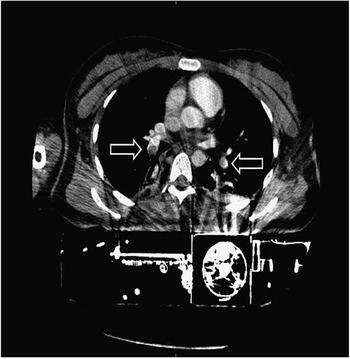

A change of the automated chest compression device to the AutoPulse® device (Zoll Medical GmbH, Chelmsford, MA, USA) was necessary as LUCAS devices do not fit into the gantry of our CT due to their height. At min 25 the multidetector CT imaging was initiated in a 64-slice CT scanner (Light Speed VCT, GE Healthcare, Waukesha, Wisconsin, USA). A scout scan was performed while running the AutoPulse device (Figure 1). In order to do this, we administered a contrast bolus IV, followed by two minutes of automated chest compressions for distribution. The mCPR device was put on hold shortly, whilst the whole body CT was performed. Contrast-enhanced CT of the chest showed a central pulmonary embolism of both sides (Figure 2).

Figure 2 Contrast enhanced chest CT showing central pulmonary embolism of both sides (arrows).